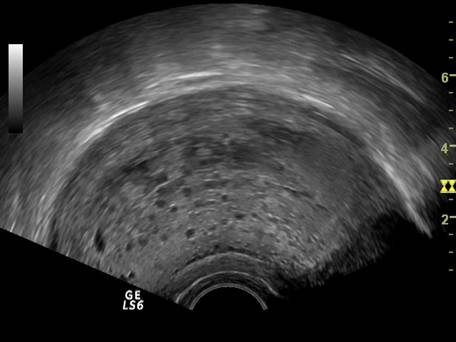

9.Sarcina si fibromul uterin

Cea mai comuna tumora uterina - leiomiomul - poate fi detectata si masurata inca de la inceputul sarcinii. Fibromul poate complica sarcina in functie de marime si pozitie. Nodulul subseros pediculat foarte rar se poate complica, in schimb nodulul submucos sau intramural creste riscul de avort spontan sau nastere prematura, dar peste 75% din aceste paciente duc sarcina la termen. Cea mai frecventa complicatie a fibromului in sarcina este necroza aseptica (25%) de obicei moderata, ea poate aparea si in lauzie. Cresterea fibromului in sarcina a fost notata in circa 22% dintre fibroame.[12]

Fibromul apare de obicei hipoecogen in uterul gravid, trebuind masurat si observat pe parcursul sarcinii.

Fig nr. 93. Nodul fibromatos subseros si intramural cu degenescenta calcara

( sageata) la o sarcina de 7 saptamani